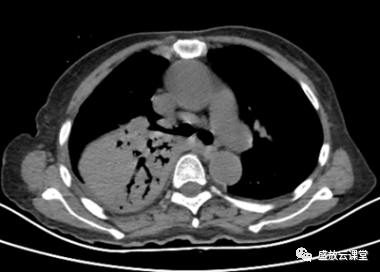

【病例】肺淋巴瘤(MALT)一例CT影像-2

【病例】肺淋巴瘤(MALT)一例CT影像-3